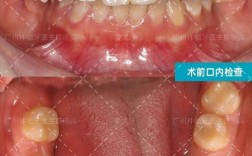

- 术前评估:通过CBCT(锥形束CT)测量牙槽骨厚度、高度,判断骨缺损范围,设计植入方案。

牙脸护理:保障种植成功的关键